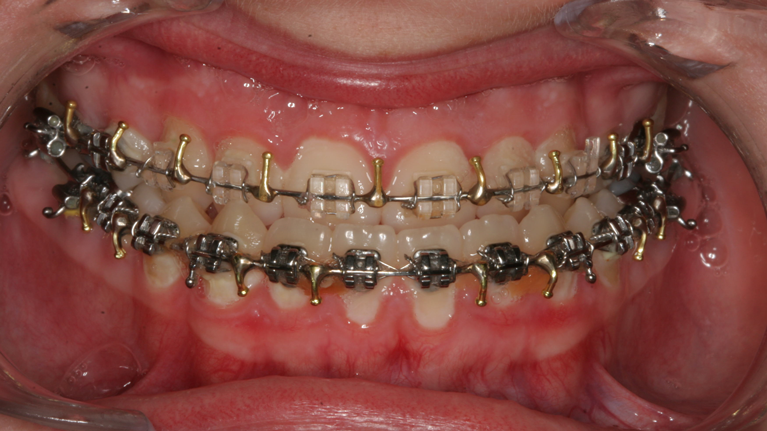

Til konferencen møder du en kirurgisk specialtandlæge fra Kæbekirurgisk Afdeling, muligvis en uddannelsestandlæge og en bøjletandlæge. De fremlægger den foreløbige behandlingsplan, som de forinden har udarbejdet. Du har mulighed for at få uddybet eventuelle spørgsmål til behandlingsplanen.